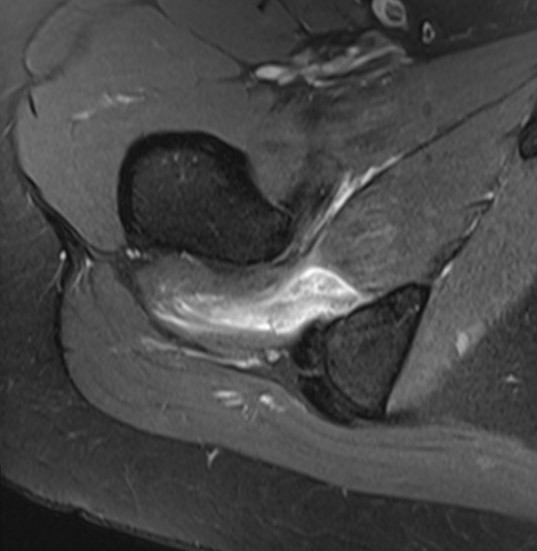

MRI

Reduced ischiofemoral space - distance between the lesser trochanter and the ischial tuberosity

Reduced quadratus femoris space - distance between hamstring tendon and iliopsoas

Inflammation / edema in quadratus femoris +/- fatty degeneration

Singer et al Skeletal Radiol 2015

- systematic review of 190 hip MRI of patients with ischiofemoral impingement

- compared to controls

- ischiofemoral space < 15 mm: sensitivity  77%, specificity 81%, accuracy 78%

- ischiofemoral space < 10 mm: sensitivity 79%, specificity 74%, accuracy 77%.